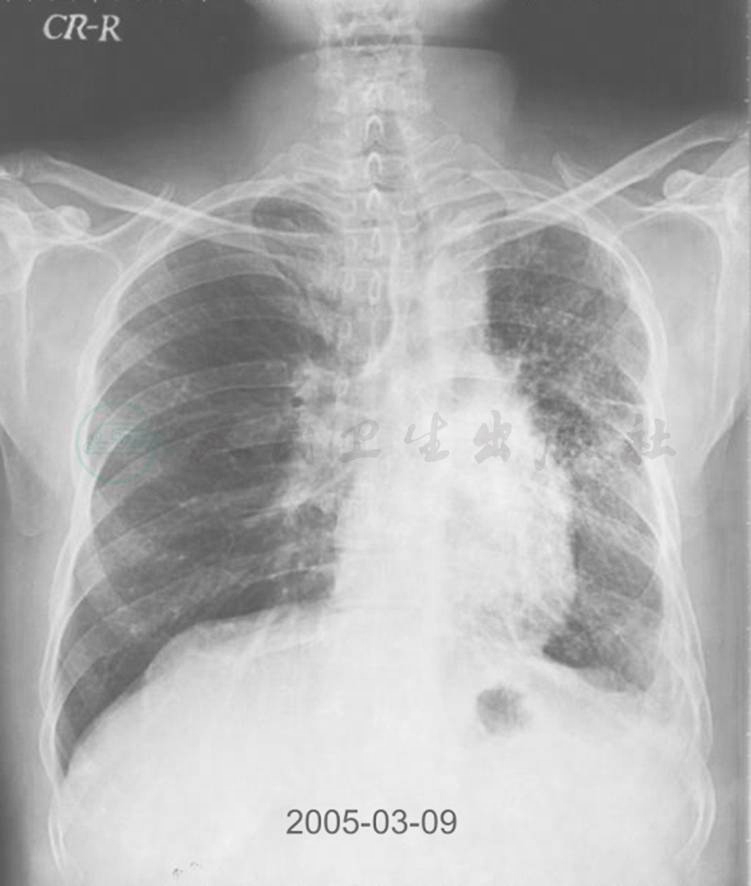

图3 12年半前胸部X线表现

胸部X线除左上肺透过度略增墙外,双肺体积大致正常

图5 10年前胸部X线表现

胸部X线可见右肺体积明显增大,透过度增加,而左肺体积相对缩小

引自:主编:.呼吸系统疑难病例诊疗辨析.第1版.ISBN:978-7-117-26415-0

图6 8年前胸部X线表现

胸部X线片可见右肺体积略有缩小,而左上肺体积明显增大伴多发大疱形成,肋膈角变钝,透光度明显增加

追溯患者既往影像学资料可了解以下信息:12年半前,X线胸片示左肺体积尚正常;10余年前,胸部CT即示左主支气管占位性病变存在,其体积及内部钙化灶逐年增大,左肺因左主支气管阻塞,肺内气体吸入受阻,形成部分肺体积膨胀不全;8年前,左肺开始出现过度充气,肺野透亮度开始增加,考虑为占位性病变形成活瓣,随着充气量增大,形成多发肺大疱,同时因反复合并肺内感染,加重了肺组织的破坏,最终导致目前的影像学表现。因患者胸部影像学异常表现并非在出生或幼年时即存在,为成年后获得性,故其左侧含气增多并非先天性发育缺陷及Swyer-James综合征所致。